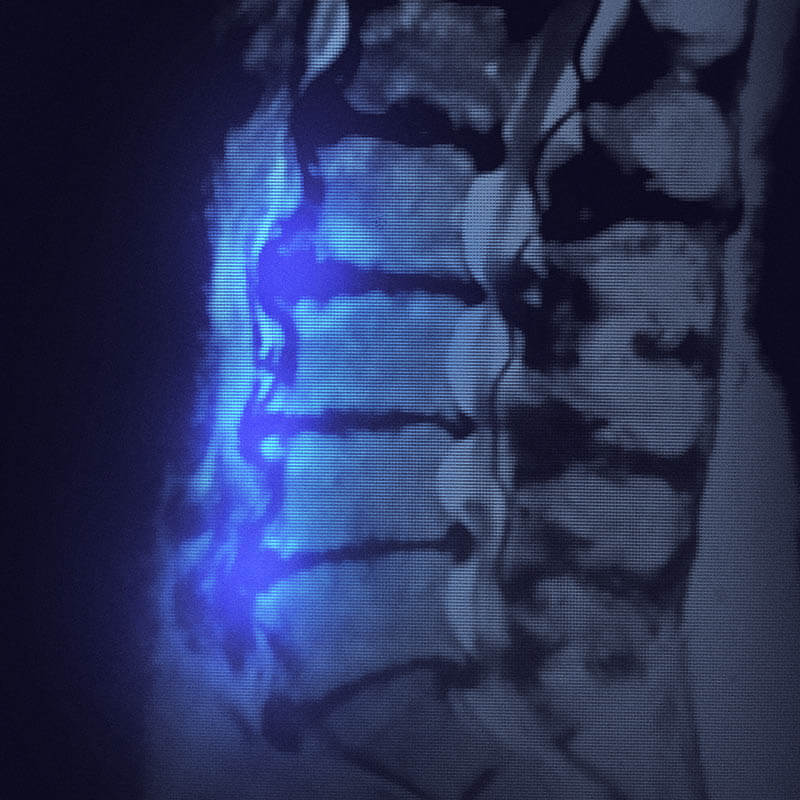

pictures of bone spurs in neck

Cervical myelopathy – MRI – Radiology at St. Vincent’s University Hospital

Mri Of Cervical Spinal Canal Stenosis Stock Photo – Download Image Now …